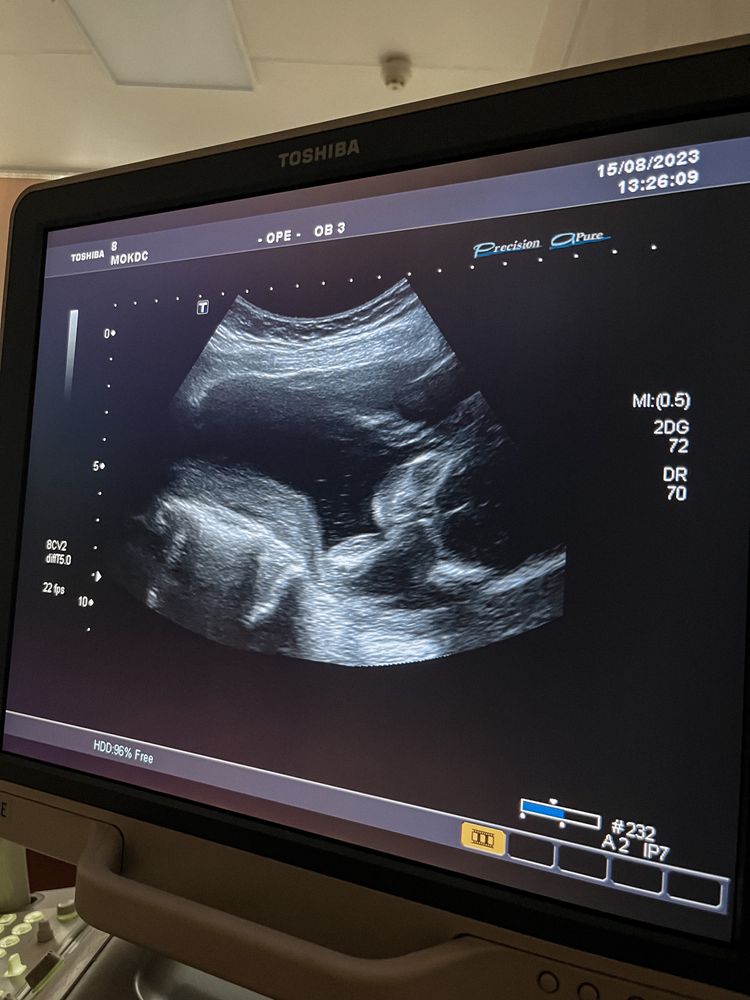

Второй скрининг (фото) и моя 20-я неделька

У меня мальчик. Второй 😀

Малыш лежал на боку спиной к нам, я перевернулась на бок и малыш тоже развернулся. Получилось увидеть личико ) Начал зевать и тереть глазки руками (на фотографии именно этот момент).

Муж в шоке, говорит там все косточки видно 😂 Ну первый раз человек на таком узи)

Шевеления ощущаю редко, хоть и с 16 недели. Думаю, от того что он любит спать лицом в другую сторону) Главное что по узи все хорошо и по сроку.